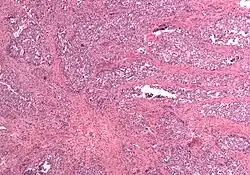

In gross appearance, MMMTs are fleshier than adenocarcinomas, may be bulky and polypoid, and sometimes protrude through the cervical os. On histology, the tumors consist of adenocarcinoma (endometrioid, serous or clear cell) mixed with the malignant mesenchymal (sarcoma) elements; alternatively, the tumor may contain two distinct and separate epithelial and mesenchymal components. Sarcomatous components may also mimic extrauterine tissues (e.g., striated muscle, cartilage, adipose tissue, and bone). Metastases usually contain only epithelial components.